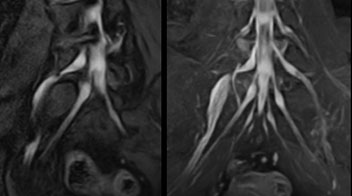

“In such case, we would then browse through axial T2-weighted MR images slice by slice and mentally reconstruct the actual situation based on both radiculography and MRI. Fortunately, NerveVIEW can now very well show nerve courses and presence of nerve compression or edema in one single image series.” “We have often seen NerveVIEW directly depict details of the nerve compression that were not observed by radiculography. Therefore, we think that with NerveVIEW we can reduce the number of invasive examinations, especially for some patients with lumbar plexus symptoms.”

“Before NerveVIEW, diagnosis by MRI alone was sometimes difficult, unless there was a strong suspicion based on clinical symptoms,” says Shoji Yabuki, MD, DMSc, Orthopedic surgeon at Fukushima Medical University School of Medicine. “This is why we routinely perform selective lumbosacral radiculography (nerve root block) and x-ray in such cases. However, radiculography can only depict nerves as far as the contrast agent reaches. When a nerve is distorted by compression, the contrast agent will not pass through this compressed area, preventing us from evaluating the full nerve compression.”

Implementing NerveVIEW without lengthening exam time “The source images of NerveVIEW exhibit a contrast similar to STIR or fat-suppressed T2-weighted images. So, in our neurography exams we are replacing the 2D T2-weighted coronal sequence with 3D NerveVIEW. With this, we add a lot of useful information without adding scan time. This is important for patients with severe lower extremity symptoms, as they often find it difficult to maintain still during the whole MRI examination, so the exam should be as short as possible.” “We have currently implemented 3D NerveVIEW on our Achieva 3.0T dStream MRI system only. Because the 3D NerveVIEW method is based on a background signal suppression technique, we decided to use the high SNR of our 3.0T MRI system for obtaining the best possible visualization of peripheral nerves,” says Tanji. “Where NerveVIEW of the lumbar plexus is currently used as a subroutine scan for patients with strong lower limb symptoms, its use for visualization of the brachial plexus, is currently limited to special cases such as schwannomas and neuritis, usually only 1 or 2 cases per month.”

The addition of the nerve-selective NerveVIEW sequence to its spine MRI protocol has given NFMC competitive advantages, according to Tanji. “Since we started including NerveVIEW routinely, the demand for lumbar spine MRI examinations has increased, especially for pre-surgical planning purposes and for patients with chronic lower extremity symptoms,” he says. “Moreover, because no other hospitals in our region are doing nerve plexus imaging yet, we often receive referrals for MR neurography studies from other hospitals even if they have an MRI scanner. Some requests come from as far as 100 km away. NerveVIEW definitely provides us a competitive advantage.” “Based on our experience, we can certainly recommend NerveVIEW to other centers,” Dr. Yabuki adds. “The sequence opens up many possibilities to facilitate the diagnosis of lower extremity pain and to inform our decision-making regarding therapy and surgery.”